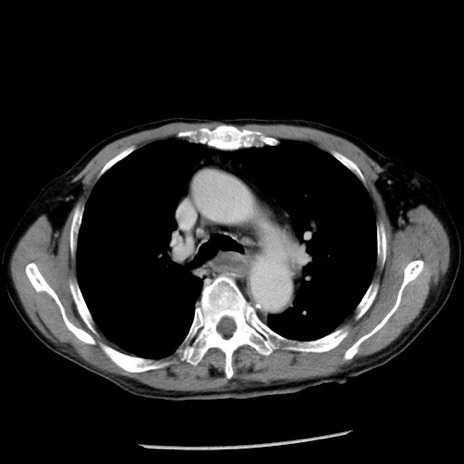

冠状断像

【症例】80歳代男性

【主訴】嘔吐

【現病歴】昨晩2回嘔吐あり、今朝になっても嘔吐あり。来院。

【既往歴】胃潰瘍

【身体所見】意識清明、BT 37.6℃、BP 166/95mmHg、HR 100bpm、SpO2 97%、腹部:平坦・軟、腸蠕動音聴取良好、圧痛なし。

【データ】WBC 21900、CRP 1.46